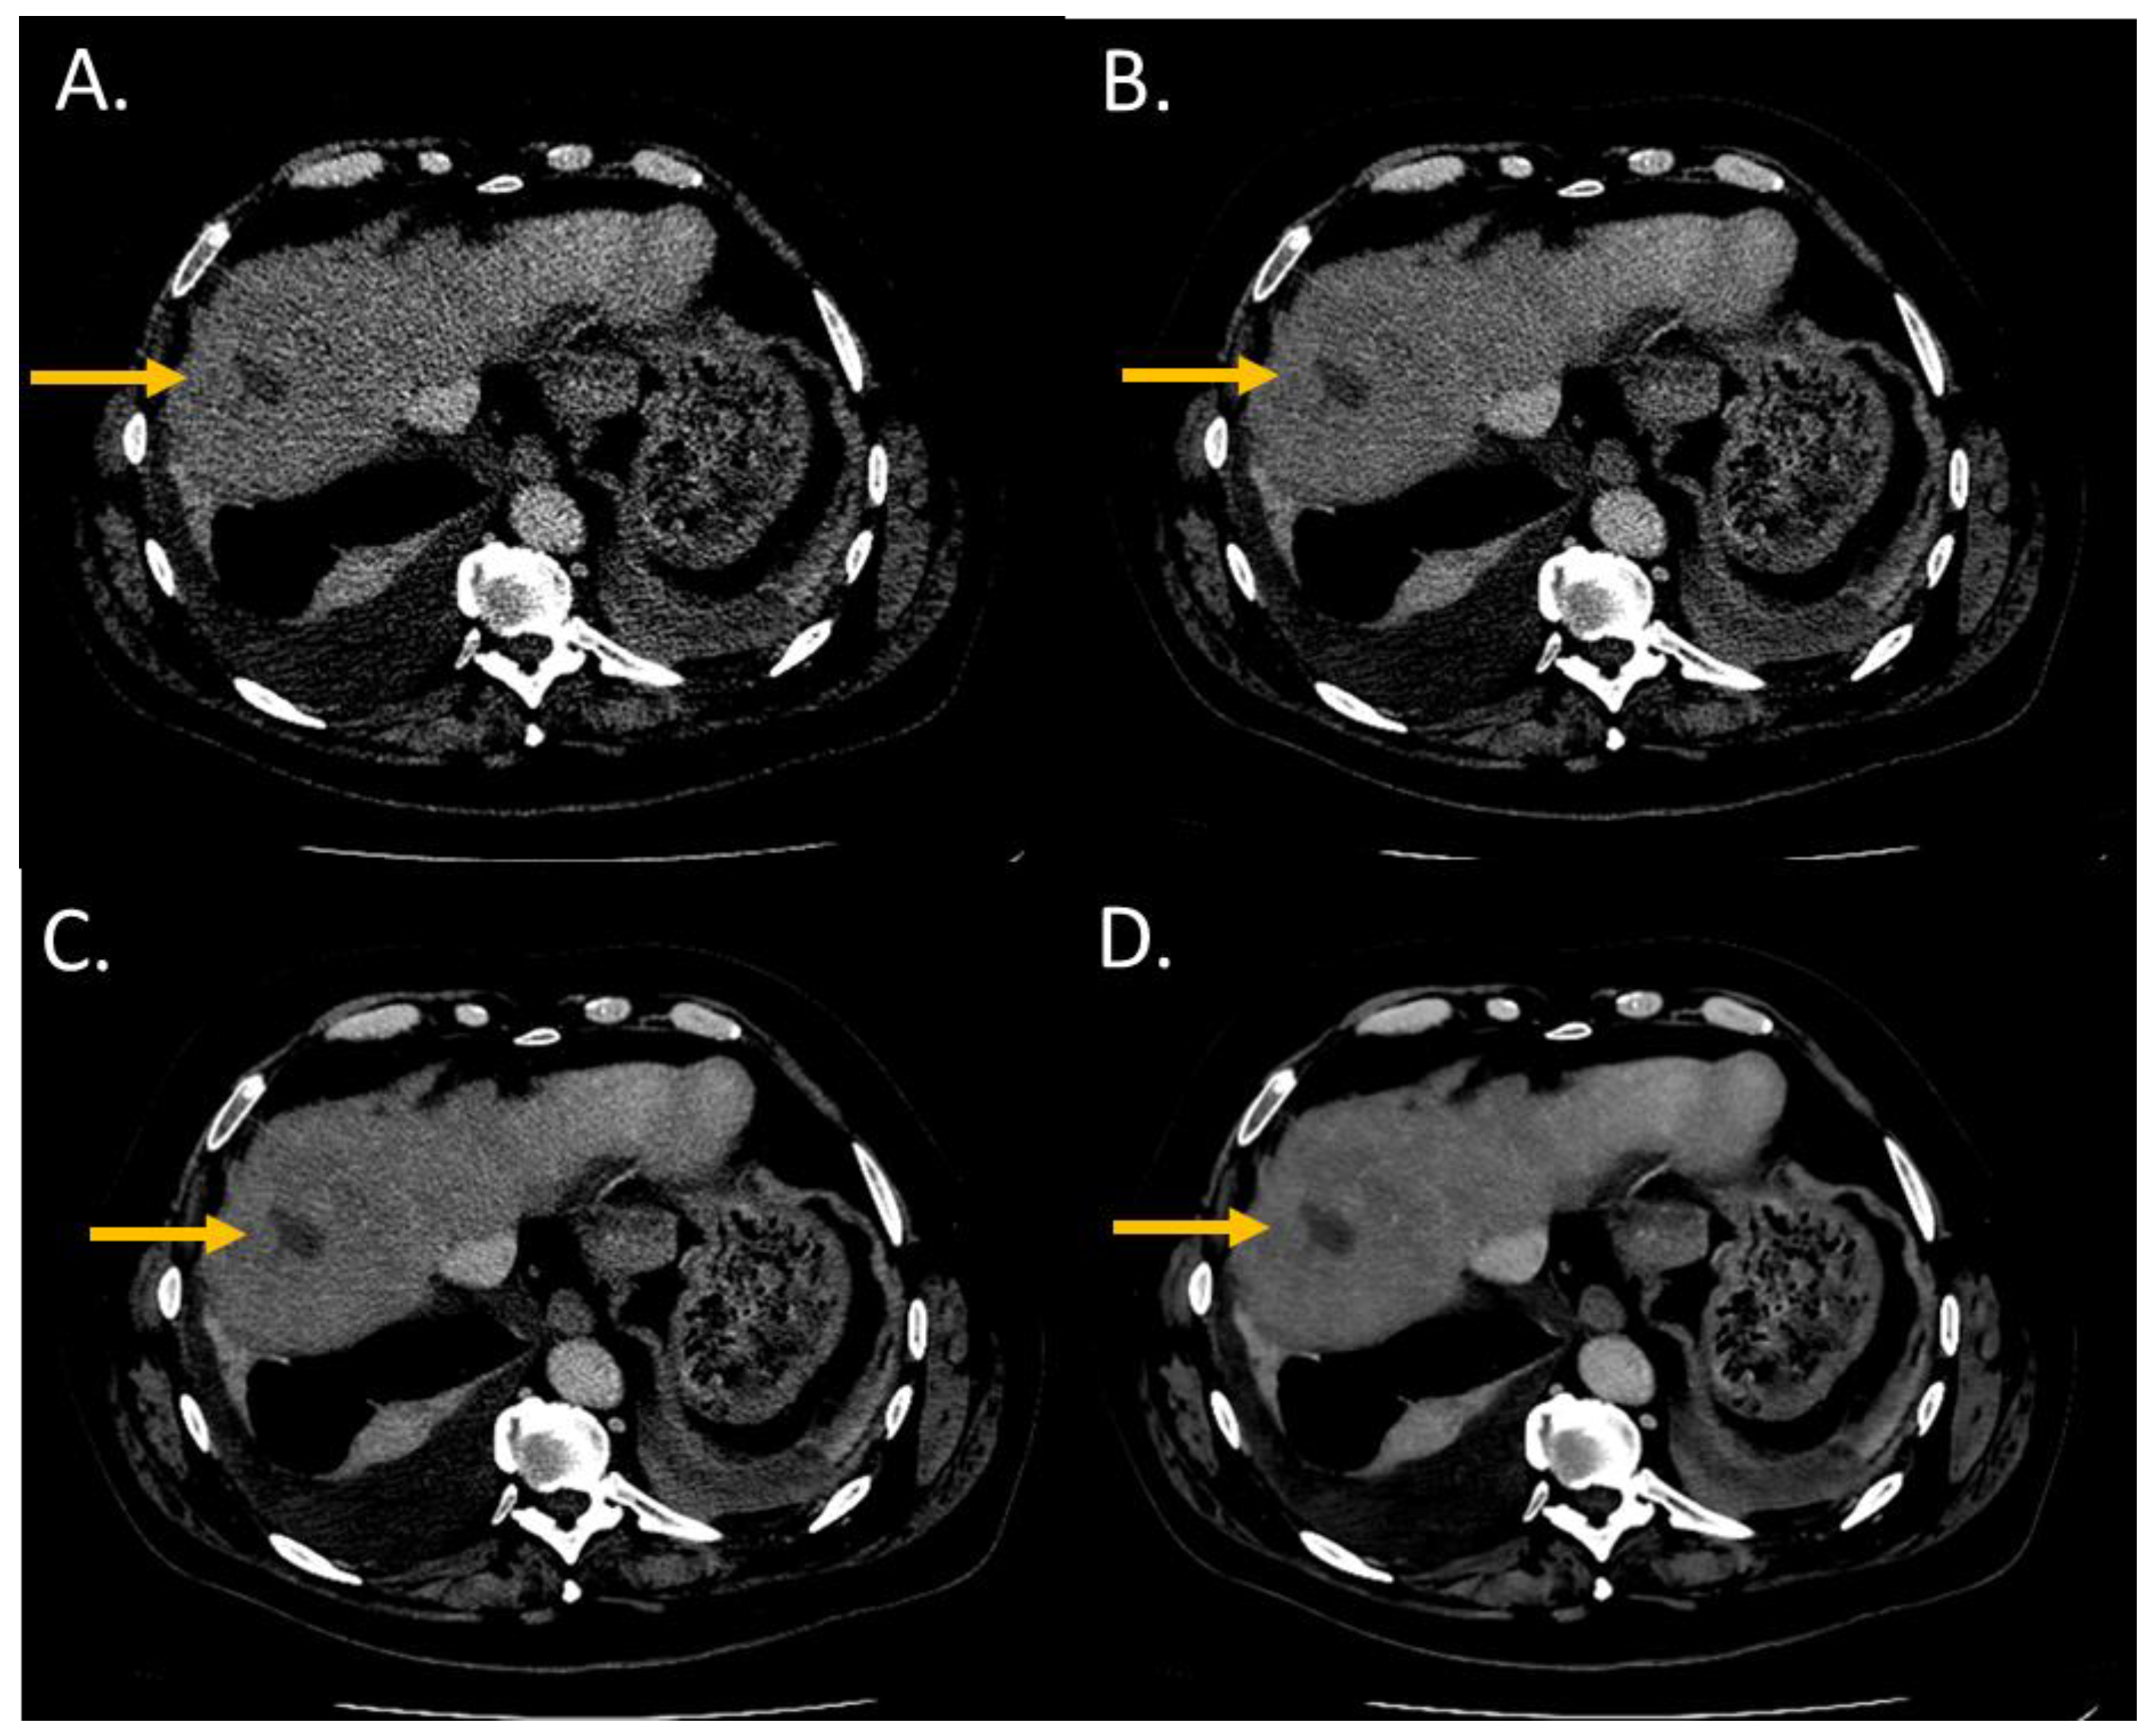

The conspicuity score significantly increased from i4 to the Standard level and from the Standard to the Smoother level (p < 0.05) (Figure 2 and Figure 3). The conspicuity score was ≥4 for 37% with i4, 53% for the Standard, 80% for the Smooth, and 93% for the Smoother level.

Figure 3.

Lesion conspicuity score of liver CT images (WL: 90 HU; WW: 190 HU) of a man (64 years old, SSDE: 10.24 mGy; average scan size 34.6 cm) with a pancreatic cancer and liver metastasis of 2.70 mm of large axis in segment VIII. (A) iDose4 level 4; lesion conspicuity score: 3; (B) Precise Image, Standard; lesion conspicuity score: 3; (C) Precise Image, Smooth; lesion conspicuity score: 4; (D) Precise Image, Smoother; lesion conspicuity score: 5.